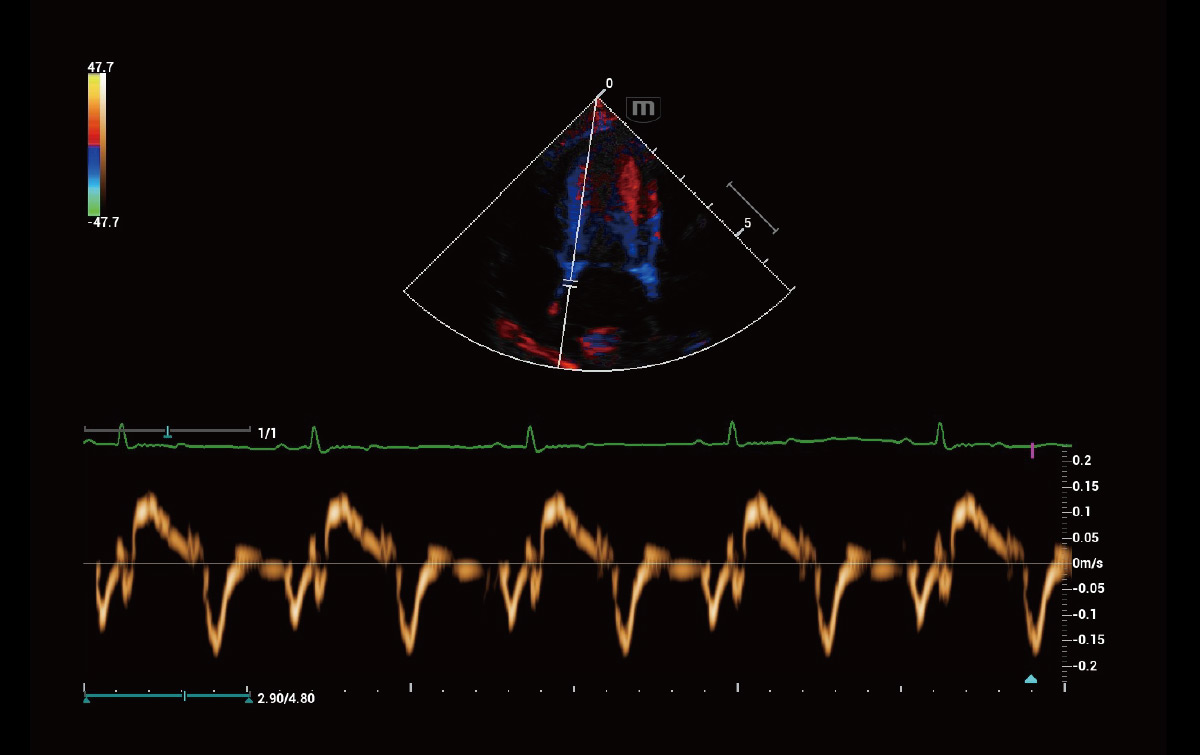

Análisis cuantitativo del movimiento y sincronización del miocardio – TDI QA

TDI QA con un máximo de 8 ROI permite análisis simultáneos de 8 regiones del miocardio, incluida la velocidad del movimiento del miocardio, la tensión del miocardio, la tasa de tensión y la sincronía del miocardio.

Evaluación del movimiento miocárdico independiente del ángulo – TT QA

El seguimiento de tejidos con análisis cuantitativo (TT QA) rastrea el movimiento del miocardio mediante la detección de patrones de motas 2D y proporciona una evaluación precisa e independiente del ángulo del movimiento del miocardio.